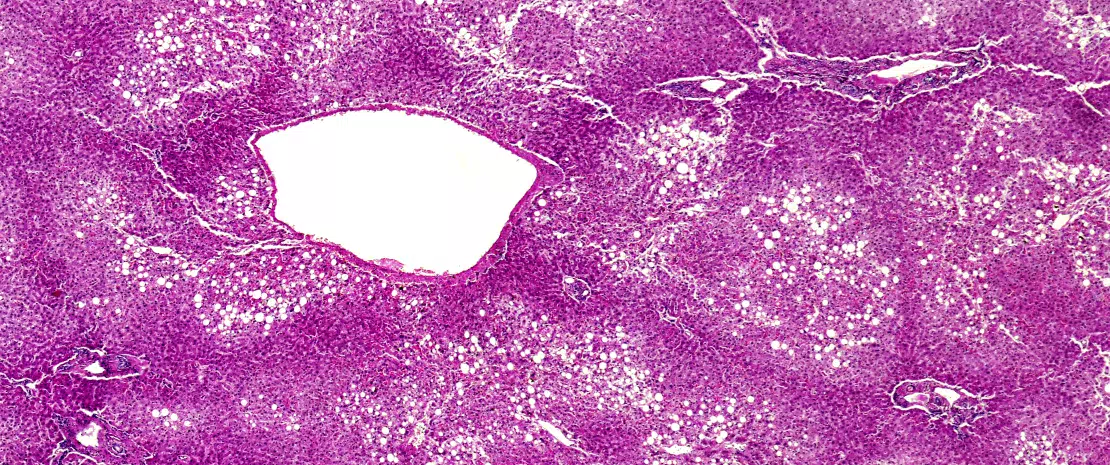

Non-alcoholic fatty liver disease (NAFLD) is the most common liver disease in western countries and affects 25-30% of the general population. NAFLD is classified into simple fatty liver disease with no or minimal inflammation, and steatohepatitis (NASH), which is characterized by steatosis, inflammation and fibrosis. NASH may lead to cirrhosis, which is a risk factor for hepatocellular carcinoma (HCC). NAFLD is the hepatic manifestation of metabolic syndrome.